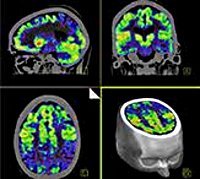

Позитронно-эмиссионная томография головного мозга в неврологии чаще всего назначается для оценки метаболических процессов мозговой ткани, таких как утилизация кислорода, метаболизм глюкозы, капиллярная перфузия и перфузия, аффинность специфических рецепторов и их количество. С помощью полученной информации вы можете выявить аномалии в активности клеток головного мозга, которые возникают на ранних стадиях заболевания. Из-за этого многие неврологические патологии диагностируются гораздо раньше, чем при КТ или МРТ.

При сосудистых заболеваниях ПЭТ-КТ может выявлять даже небольшие гемодинамические нарушения, определять степень тяжести и распространенности и дифференцировать сосудистую деменцию от других ее типов. При диагностике объемных мозговых процессов ПЭТ используется для раннего выявления опухолей, его дифференциальной диагностики с другими объемными образованиями (абсцесс, киста) и оценки степени злокачественности. Кроме того, методика используется для уточнения размеров и пределов новообразований, которые не четко визуализируются при КТ или МРТ, оценки результатов радиологического лечения и химиотерапии, радикального удаления опухоли.

При эпилепсии процедура назначается для определения расположения эпилептического очага. Используя этот метод, нейрохирурги определяют наиболее важные функциональные области мозга, чтобы избежать повреждений во время операции. Острые поражения и посттравматический период являются показаниями для ПЭТ-КТ в тех случаях, когда данные КТ или МРТ не полностью объясняют клиническую картину, присутствующую у пациента.